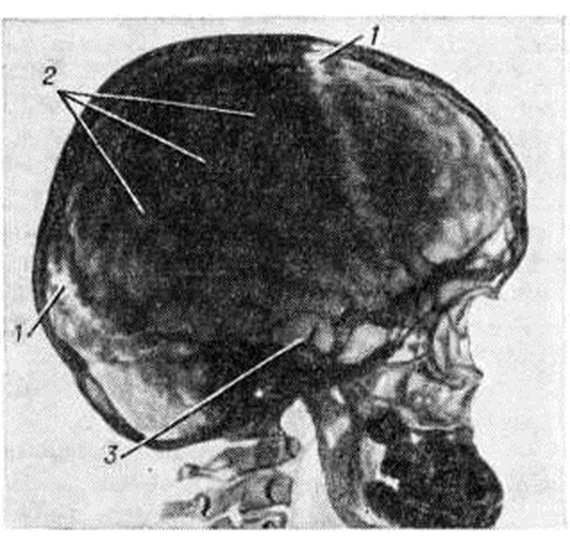

Краниография (смотри) позволяет не только поставить диагноз Гидроцефалия, но и определить её форму. При сообщающейся Гидроцефалия, развившейся в раннем детском возрасте, форма черепа шарообразна. Кости свода черепа истончены, рельеф внутренней костной пластинки сглажен (рисунок 6). Отмечается уплощение черепных ямок с углублением передней черепной ямки, расхождение швов черепа к незаращение родничков. Вход в турецкое седло расширен. Для окклюзионной Гидроцефалия характерны выраженные пальцевые вдавления в костях свода черепа, расхождение швов (рисунок 7), расширение диплоических вен, вдавления на кости от поперечного синуса и наличие расширенных эмиссариев. При окклюзии на уровне задней черепной ямки нередко наблюдается отклонение спинки турецкого седла кпереди, истончение её и сужение входа в турецкое седло. При окклюзии в области водопровода мозга дно турецкого седла углублено, спинка его отклонена кзади. При закрытии одного из межжелудочковых отверстий череп имеет асимметричную форму.